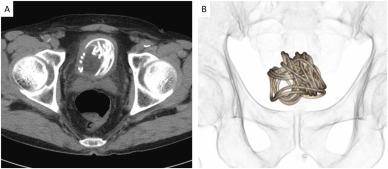

“Primeiro realizamos um ultrassom e identificamos um objeto grande na bexiga do paciente. Depois fizemos um raio-x, que revelou um corpo estranho enrolado em forma de fio. Em seguida, fizemos uma tomografia que nos ajudou a escolher o melhor jeito de tirar a corda e usamos um programa de computador em 3D para nos direcionar. Percebemos que seria impossível puxar a corda pelo pênis”, disse Toshiki Kijima, professor de urologia na Dokkyo Medical University, autor do documento.

Legenda: Imagens obtidas pela equipe médica

Foto: Reprodução/Urology Case Reports